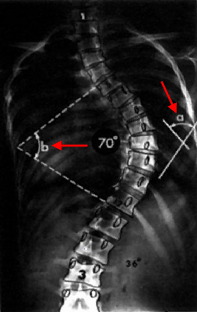

يتم التشخيص بالفحص السريري و الأشعة , و سوف نذكر طريقة قياس زاوية الإنحناء من الأشعة و التي تُسمى طريقة كوب Cobb Method و كذلك يُطلق على الزاوية زاوية كوب Cobb Angle . و تُقاس من صورة الأشعة السينية بالطريقة التالية:

" تعيين الفقرات التي تحدد الطرف العلوي و الطرف السفلي للإنحناء. و هذه الفقرات هي أشد فقرات الإنحناء ميلاناً تجاه الجهة المُقعرة للإنحناء.

" بعد تعيين الفقرتين , يُرسم خط مستقيم يمر بالطرف العلوي للفقرة العلوية للإنحناء و خط مستقيم آخر يمر بالطرف السفلي للفقرة السفلية للإنحناء.

" تُحسب الزاوية التي تقع عند تقاطع هذين الخطين و هي زاوية الإنحناء.

على اليمين صورة أشعة سينية X-Ray تبين كيفية حساب درجة زاوية إنحناء الجنف (زاوية كوب Cobb Angle) , الزاوية b هي زاوية الإنحناء و تساوي الزاوية a , و تساوي 70 درجة. على اليسار صورة لأشعة مقطعية محوسبية (بالحاسوب) Computerized Tomographic Scan CT و حساب الزاوية بالكمبيوتر.